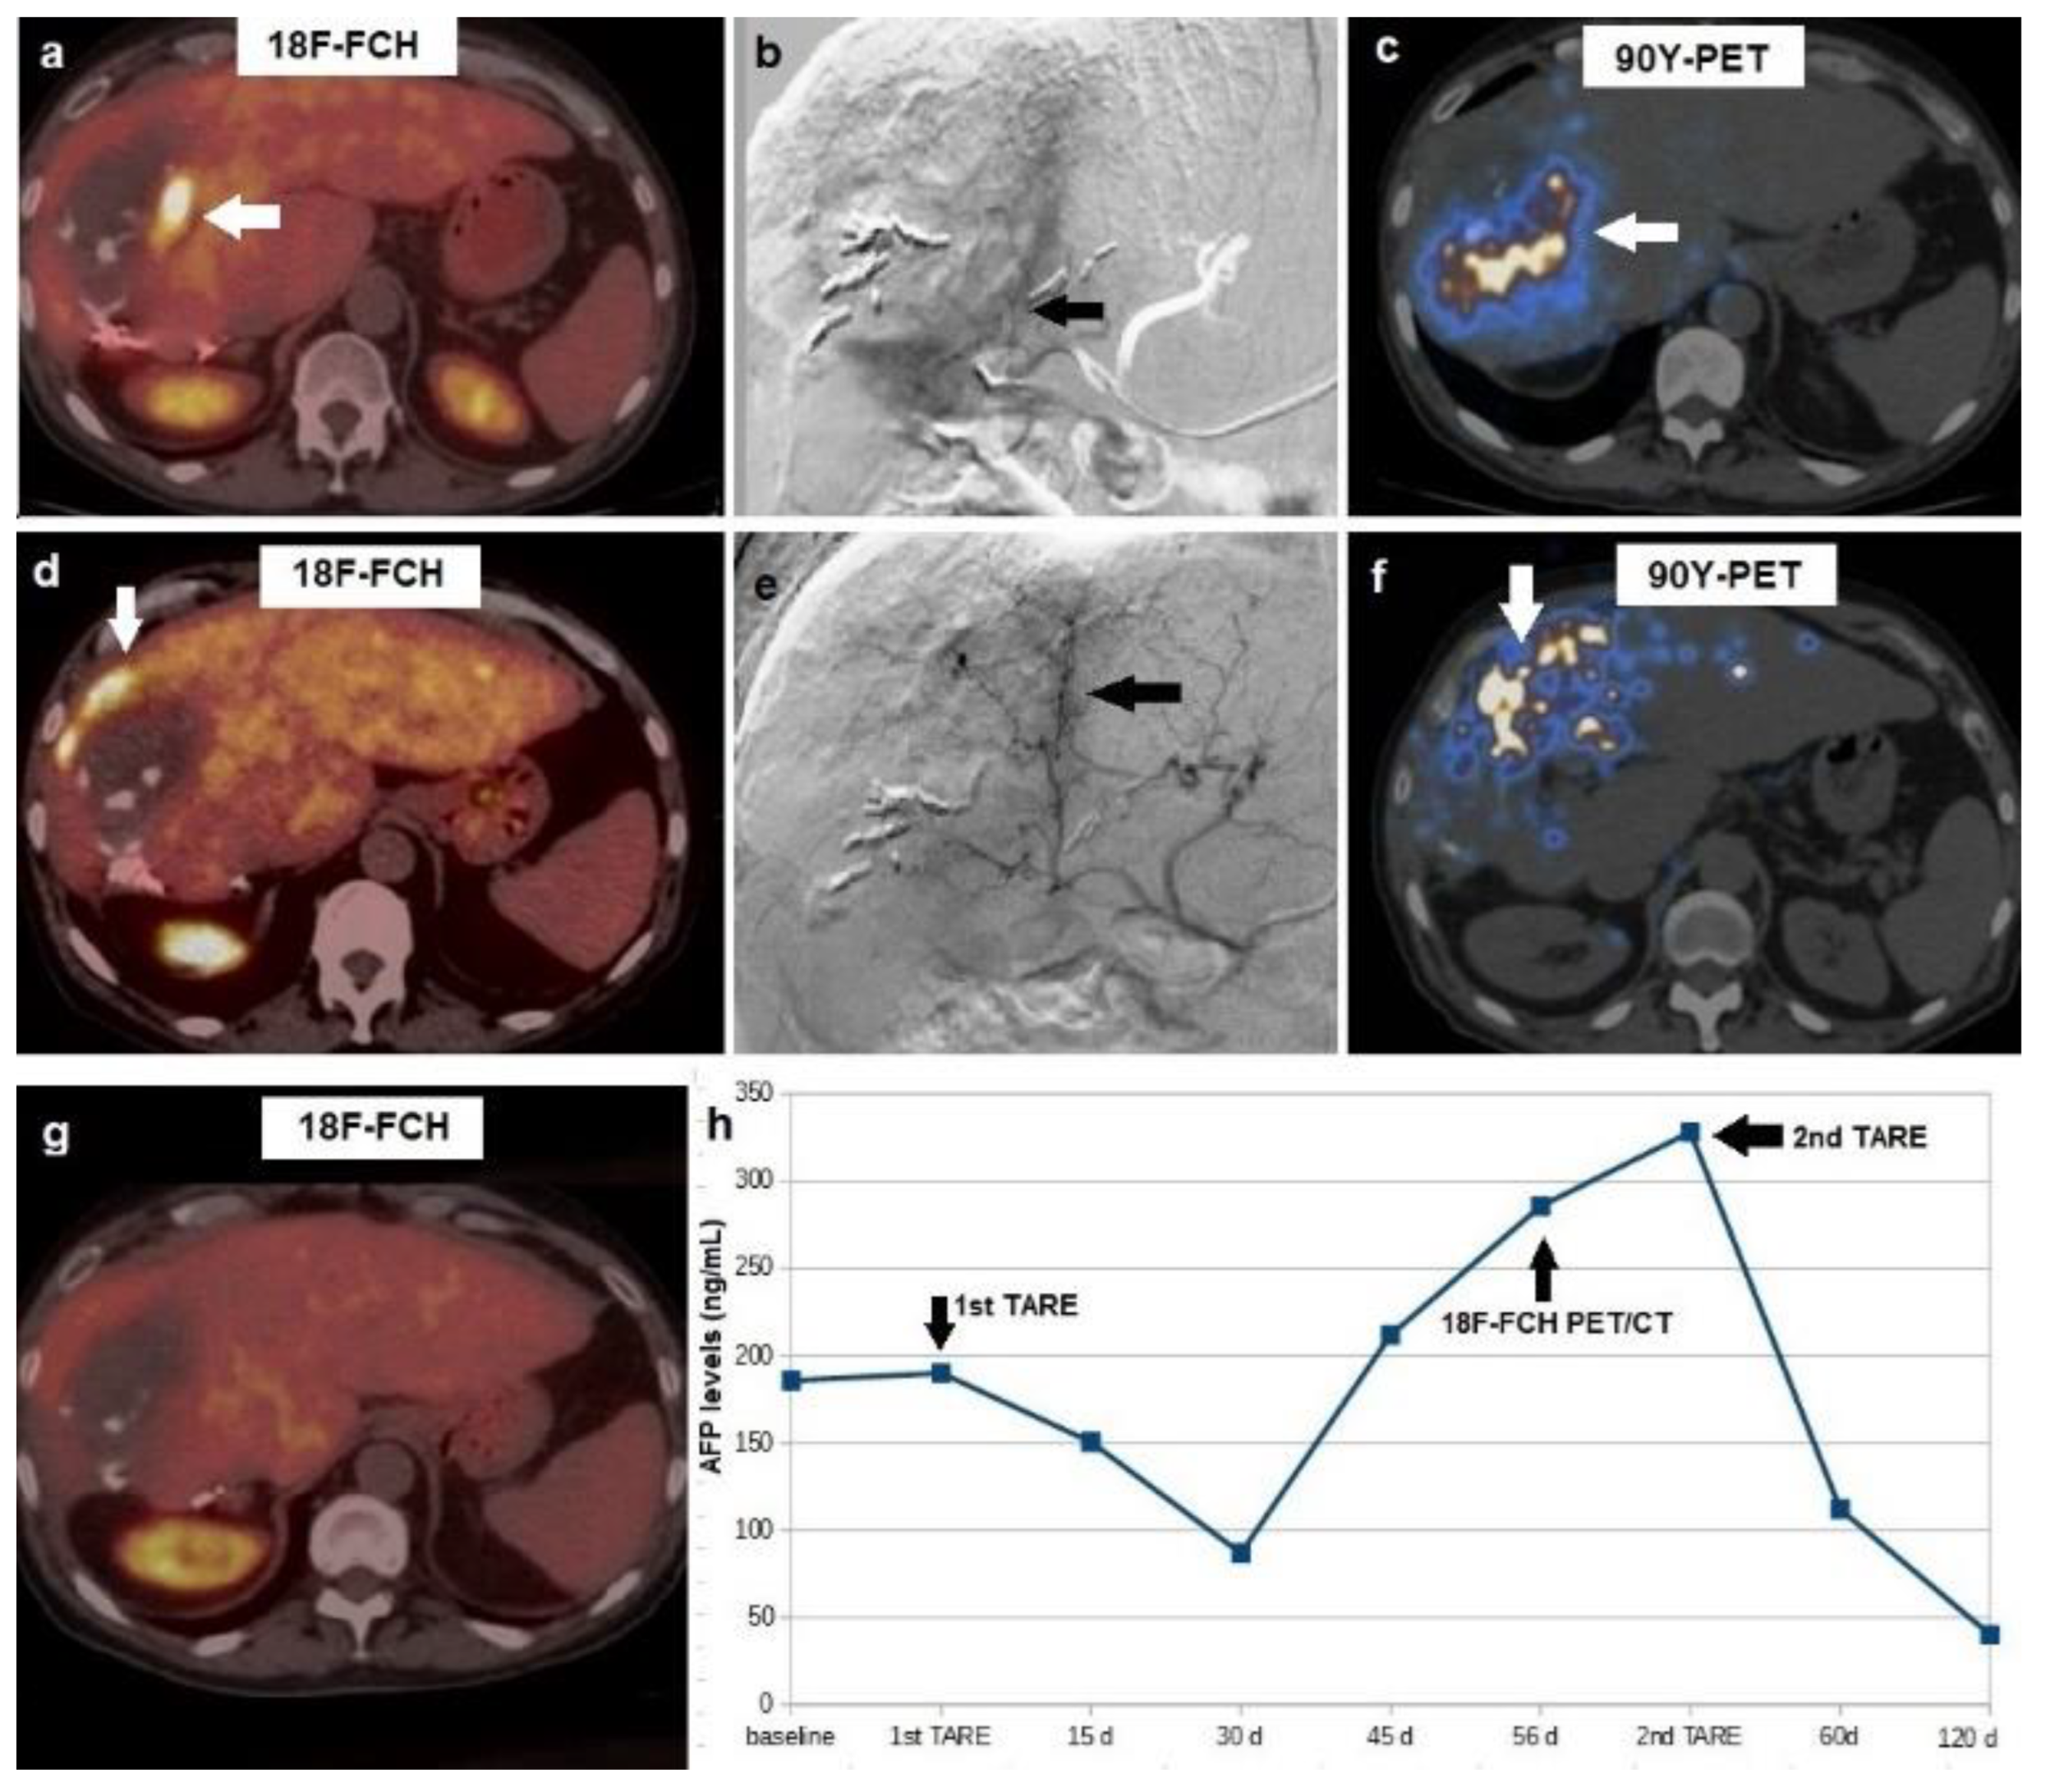

Figure 3. A 57-year-old male, affected by HCV-related cirrhosis and HCC in the right hepatic lobe, previously treated with laser ablation and surgical resection, referred to our center for 90Y-TARE. (a) Pre-treatment 18F-choline PET/CT demonstrated increased tracer incorporation in the infero-medial portion of the HCC lesion (arrow), which showed a central necrotic, hypodense area at co-registered CT slice. (b) Pre-TARE angiogram, performed after selective catheterization of the arterial feeder of the active tumor tissue detected by PET/CT, showed the hypervascularized tumor (arrow). (c) 90Y-PET acquired 4 h after TARE demonstrated 90Y-microsphere deposition in the treated tumor (arrow). (d) At 8-weeks post TARE PET/CT, a new-onset metabolically active HCC tissue was detected in the superior rim of the lesion (arrow), in spite of complete response of the tumor tissue previously located in HCC’s infero-medial portion. Therapeutic decision was to carry out a second 90Y-TARE: (e) a new angiogram was acquired after selective catheterization of the arterial branch for the upper hepatic segments (arrow). (f) 90Y-PET at 4 h post TARE demonstrated 90Y-microsphere accumulation in the superior portion of the HCC lesion. (g) Post-treatment PET/CT at 8 weeks after the second 90Y-TARE showed complete metabolic response. (h) Graph representation of alphafetoprotein trend during the different phases of the patient’s clinical management. Overall survival was 25 months.

Post-TARE PET/CT affected patients’ clinical management in 10 out of 21 cases (47.6%). In particular, a second 90Y-TARE treatment was performed in eight patients with evidence of metabolically active HCC remnant (n = 7) or new-onset lesion (n = 1). In such cases, a further angiography was performed before the second 90Y-TARE, and vascular imaging was accurately examined in order to identify and selectively catheterize the arterial branch supplying the metabolically active tissue disclosed by 18F-FCH (n = 7) or 18F-FDG (n = 1) PET-imaging. In all these patients, complete metabolic response was registered after PET-guided 90Y-TARE (Figure 3).